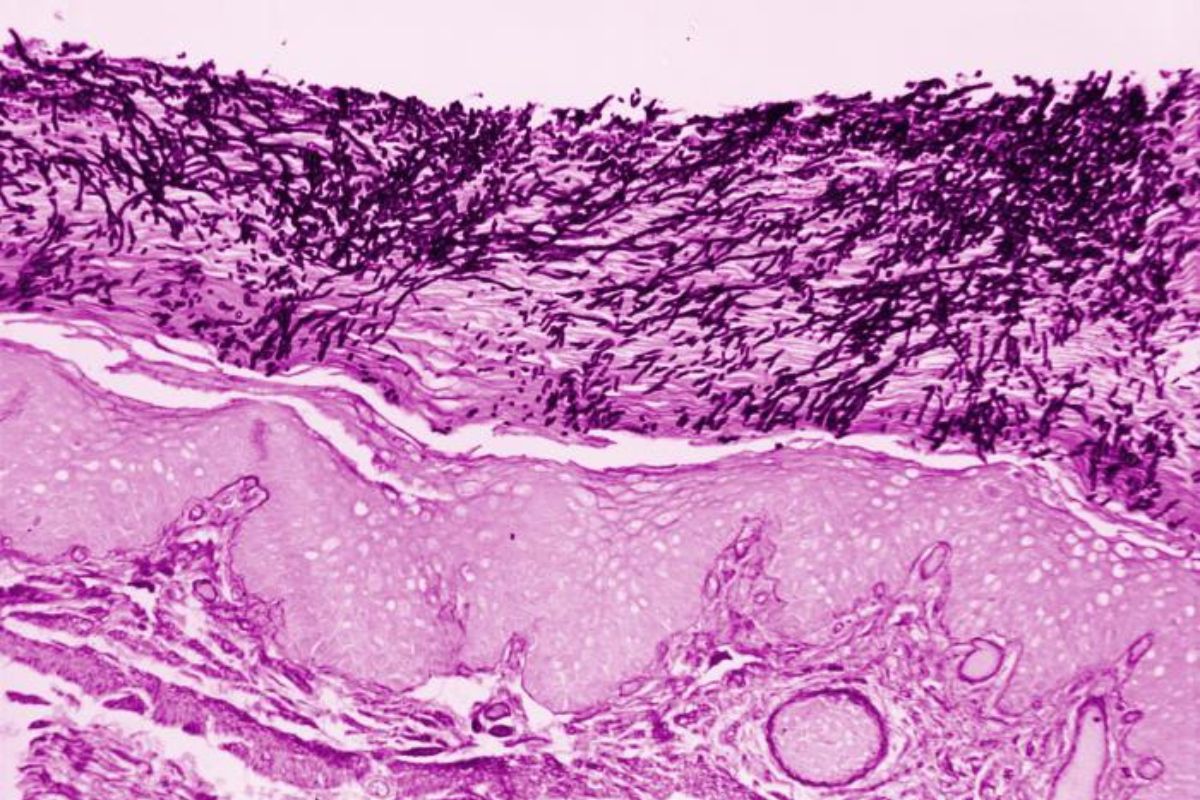

Candida albicans biofilm development occurs in four distinct stages (Rodriguez et al., 2020):

Research has shown that when Candida albicans is cultured in the lab, a mature biofilm forms within 24 hours and can be visualised by the unaided eye as a cloudy surface structure, and with a microscope as an organized collection of different cell types (Nobile et al., 2016).